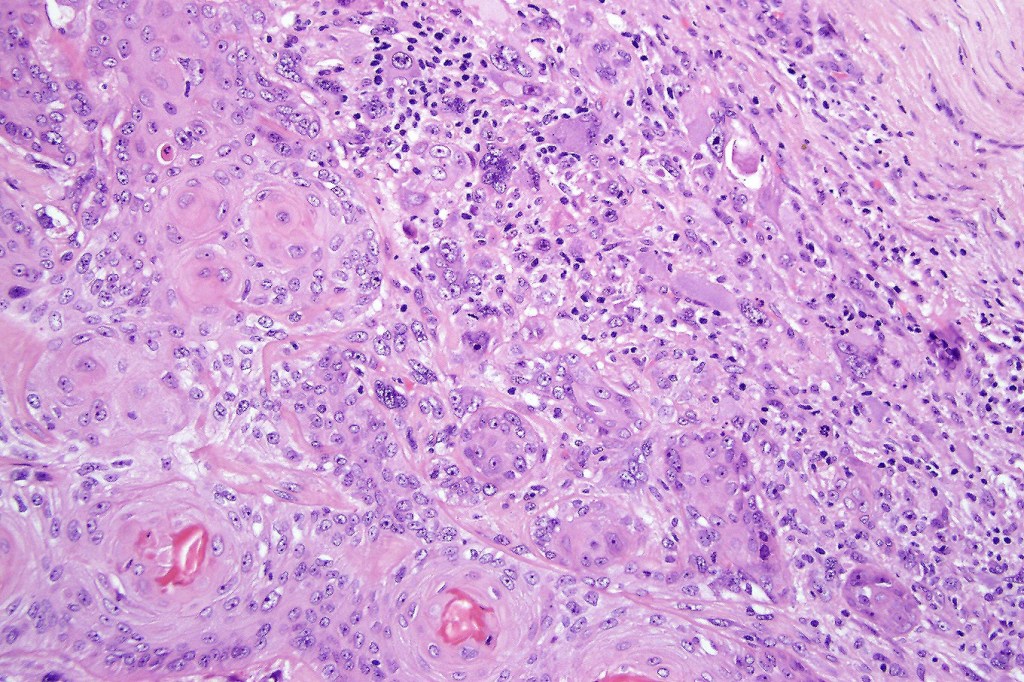

•Biphasic tumor

•Admixture of squamous carcinoma & pleomorphic spindled cell, osteoid, chondroid, MFH-like +/- osteoclast-like giant cells & rarely, smooth muscle, skeletal muscle, myofibroblastic or angiosarcomatous elements

•Mesenchymal element variable CD10, CD68, CD99 & lineage specific markers +ve; scattered cells may show weak keratin expression